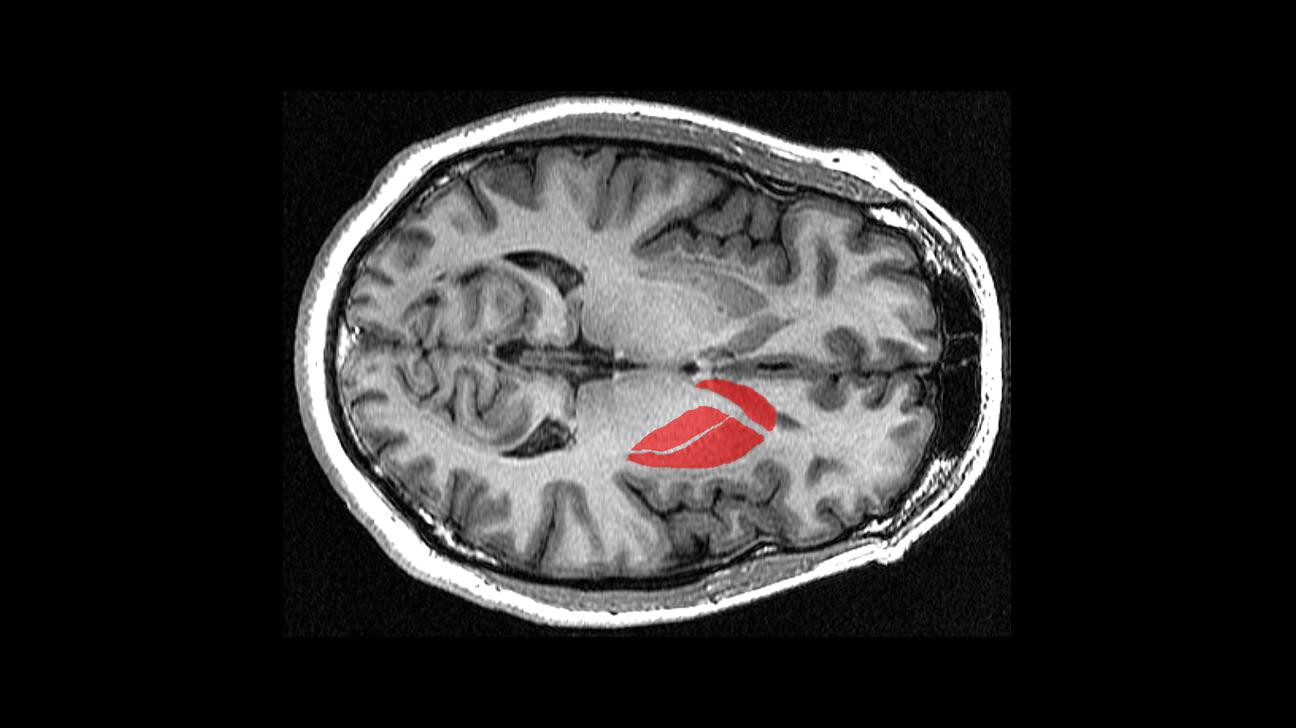

Une tumeur cérébrale peut se développer dans n’importe quelle zone du cerveau.

La localisation de ces tumeurs dans le cerveau rend le traitement beaucoup plus compliqué.